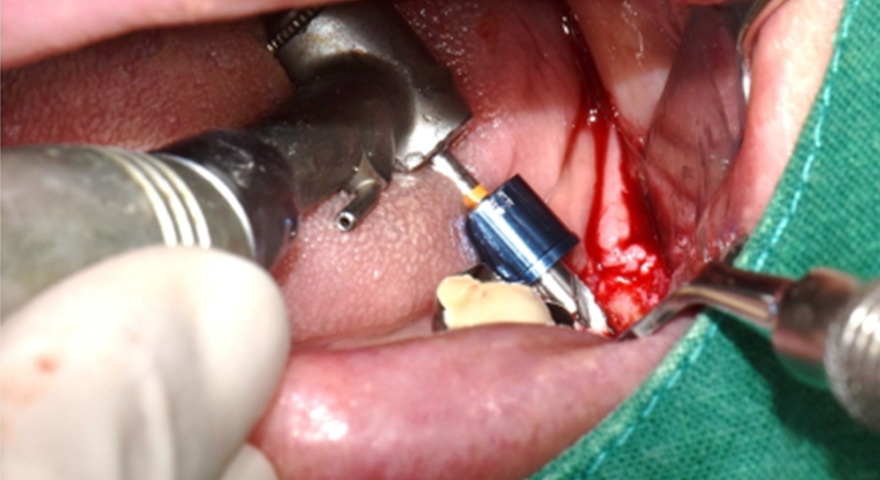

Після проведення стандартної імплантації в ділянках з оголеною різьбою було застосовано техніку DUK: на імплантат наносили спочатку пастоподібний матеріал, далі — гранули, після чого укладали мембрану та закривали клапті швами без натягу. Всі пацієнти отримували антибіотики (амоксицилін) та знеболення (ібупрофен), а через шість місяців — проходили контроль та біопсію ділянки.

Рис. 2. (A) Пацієнт із виявленою необмеженою (non-contained) втратою кісткової тканини та оголенням імплантату з букального боку на момент встановлення імплантату. (B) Нанесення основного шару пастоподібного кісткового матеріалу перед внесенням гранульованого кісткового трансплантата. (C) Укладання колагенової мембрани з покриттям зони трансплантації — від букального до піднебінного боку — та фіксували за допомогою внутрішніх періостальних швів. (D) Через шість місяців після аугментації — візуалізується регенерація кістки з букального боку в ділянці раніше оголеної різьби імплантату.